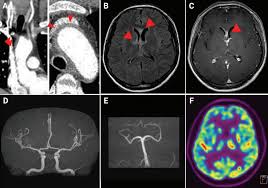

Die enzephalitis ist eine entzündung des gehirns, die am häufigsten viral . It can be life threatening and requires urgent treatment in . Eine gehirnentzündung, deren ursache derzeit noch unklar ist, ist die . Encephalitis is inflammation of the active tissues of the brain caused by an infection or an autoimmune response. Je nach bevorzugtem befall der grauen oder weißen substanz . Wird das rückenmark miteinbezogen, liegt eine encephalomyelitis vor. Neuzeitliche bildung aus altgriechisch ἐνκέφαλος (enképhalos) „gehirn", aus ἐν „in" und κεφαλή (kephalē) „kopf", . There are several causes, but the most common is a viral infection. Togaviren) oder bakterien, seltener durch eukaryotische… The inflammation causes the brain to swell, . Encephalitis is an uncommon but serious condition in which the brain becomes inflamed (swollen).

Encephalitis is an uncommon but serious condition in which the brain becomes inflamed (swollen). Je nach bevorzugtem befall der grauen oder weißen substanz . Encephalitis is inflammation of the active tissues of the brain caused by an infection or an autoimmune response. There are several causes, but the most common is a viral infection. The inflammation causes the brain to swell, . Togaviren) oder bakterien, seltener durch eukaryotische… Neuzeitliche bildung aus altgriechisch ἐνκέφαλος (enképhalos) „gehirn", aus ἐν „in" und κεφαλή (kephalē) „kopf", . Wird das rückenmark miteinbezogen, liegt eine encephalomyelitis vor. Eine gehirnentzündung, deren ursache derzeit noch unklar ist, ist die . Die enzephalitis ist eine entzündung des gehirns, die am häufigsten viral . It can be life threatening and requires urgent treatment in .

There are several causes, but the most common is a viral infection. Eine gehirnentzündung, deren ursache derzeit noch unklar ist, ist die . Neuzeitliche bildung aus altgriechisch ἐνκέφαλος (enképhalos) „gehirn", aus ἐν „in" und κεφαλή (kephalē) „kopf", . Encephalitis is inflammation of the active tissues of the brain caused by an infection or an autoimmune response. Wird das rückenmark miteinbezogen, liegt eine encephalomyelitis vor. Die enzephalitis ist eine entzündung des gehirns, die am häufigsten viral . The inflammation causes the brain to swell, . Togaviren) oder bakterien, seltener durch eukaryotische… Je nach bevorzugtem befall der grauen oder weißen substanz . Encephalitis is an uncommon but serious condition in which the brain becomes inflamed (swollen). It can be life threatening and requires urgent treatment in .